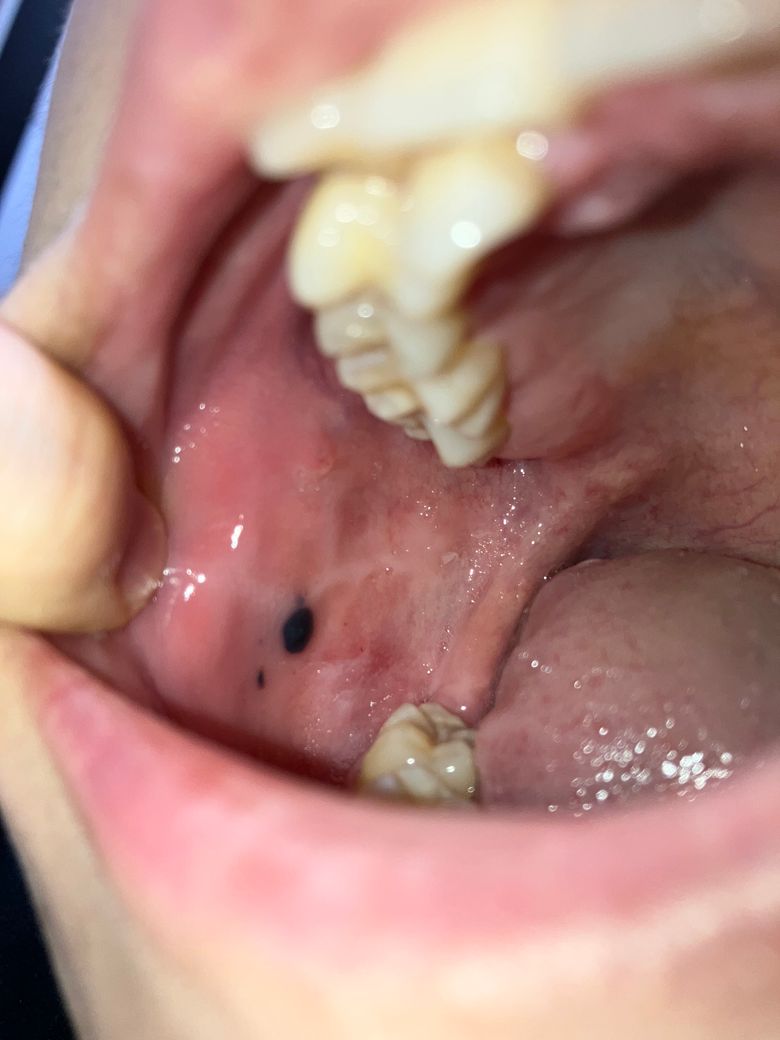

견과류 먹었는데 볼 안쪽에 까만 점 같은게

생겼어요 이게 뭔가요? 혀로 만져보면 약간 살점이 튀어나온 것 같은데 이게 뭐죠..? ……………………….…………………….

올려주신 사진만으로는 다소 제한적이나 딱딱한 견과류를 섭취하며 또는 씹는 과정에서 치아에 의해 볼 안쪽 점막에 상처와 출혈이 생겼다가 호전되었을 가능성을 생각해볼 수 있습니다.

수 일내 호전 될 것으로 생각되나 당분간 단단하고 거친 음식의 섭취는 피하고, 음주, 흡연, 자극적이거나 너무 뜨거운 음식의 섭취는 회복을 지연시킬 수 있어 피할 것을 권합니다.